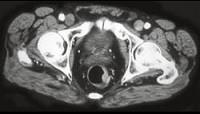

问题 男性,41岁,血便,肛诊触及左侧直肠壁一质硬小结节,结合CT所见应考虑为 ( )

选项 A.直肠腺瘤 B.直肠癌 C.直肠息肉 D.直肠转移瘤 E.直肠间质瘤

答案 B